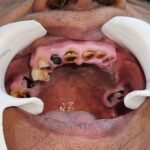

C1005 zygomatic basal implant full mouth – Ali Hasan 4

Dr. N.B. Singh